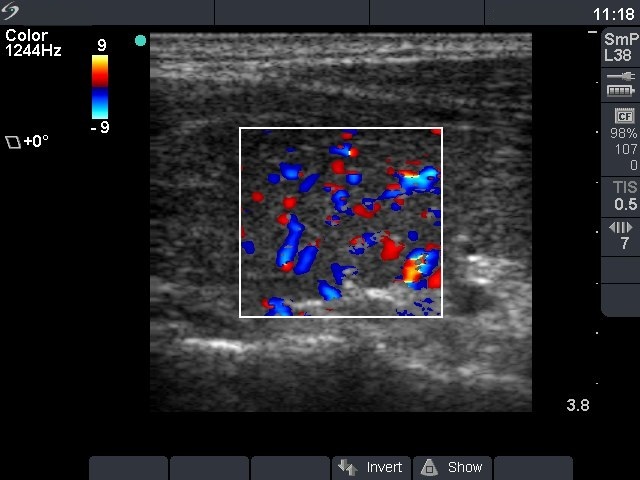

First examination (first row):

Clinical presentation: a 24-year-old man was referred for an evaluation of hyperthyroidism.

Palpation: no abnormality.

Functional state: hyperthyroidism with TSH 0.001 mIU/L, FT4 57.1 pM/L.

Ultrasonography: the thyroid was moderately hypoechogenic without any nodule. The vascularization was increased.Clinical diagnosis: hyperthyroidism caused by Graves-Basedow's disease.